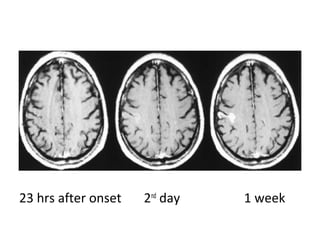

8 hrs after onset 2nd

day 1 week

6.5 hrs after onset 2nd

15 hrs after onset 2nd

23 hrs after onset 2nd